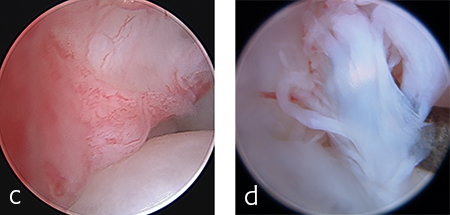

A 2.7/3.5 Pancarpal Arthrodesis was applied to the dorsal aspect of the carpus using a combination of locking and cortical screws. A 2.7 mm cortical screw was used to attach the plate to the radiocarpal bone. Five 2.7 mm locking screws were used to attach the plate to the 3rd metacarpal bone. Five 3.5 mm locking screws and one 3.5 mm cortical screw were used to attach the plate to the dorsal surface of the radius. A combination of locking and cortical screws was used to provide compression (cortical screw placed in eccentric position to provide compression across the radiocarpal joint) and achieve excellent stability and limb alignment. The incision was closed in routine fashion.

Postoperative radiographs revealed proper joint orientation and compression of the multiple antebrachiocarpal joint levels (Fig 5). Implant placement was considered excellent.

Treatment with a splint for several weeks resulted in no improvement. A pancarpal arthrodesis was performed with the 2.7/3.5 Pancarpal Arthrodesis Plate and a combination of standard cortical and locking screw fixation. An autogenous cancellous bone graft was collected from the left proximal humerus and placed at all joint levels.

Immediate postoperative images confirmed anatomic alignment and adequate carpal extension (Fig 10). At the 11-week postoperative follow-up examination, functional recovery was very good with images revealing stable implants and healing of the arthrodesis (Fig 11). The dog was then allowed to return to normal activity.